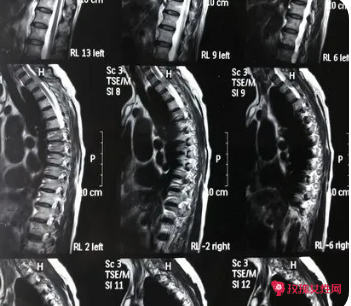

image.png